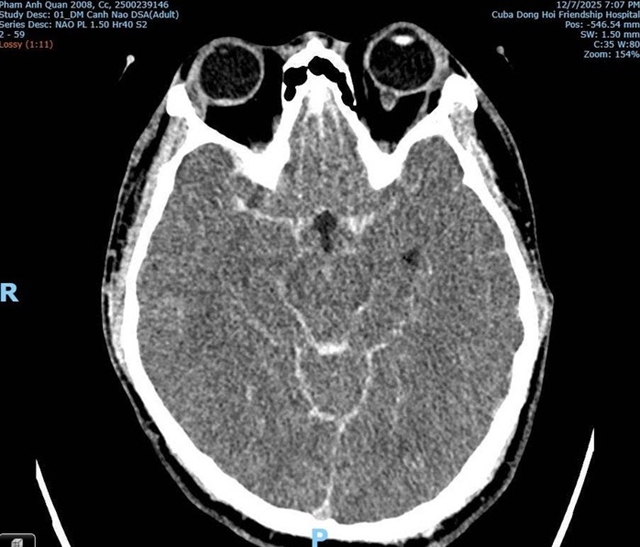

Hình ảnh CT/MRI: Xuất huyết dưới nhện do vỡ phình mạch máu não của bệnh nhân Phạm Anh Q. thời điểm tại Bệnh viện Hữu nghị Việt Nam - Cuba Đồng Hới

Phân tích từ hình ảnh chẩn đoán, bác sĩ Hùng khẳng định không ghi nhận tổn thương xương cột sống cổ, không tổn thương vòm sọ và không có dấu hiệu lực tác động đủ mạnh để gây tử vong. Ngược lại, kết quả chỉ cho thấy xuất huyết não lan tỏa kèm phù não – điển hình của vỡ phình mạch. Ông nhấn mạnh đây là nhận định chuyên môn cá nhân qua góc nhìn chẩn đoán hình ảnh; kết luận chính thức vẫn phải chờ giám định pháp y.